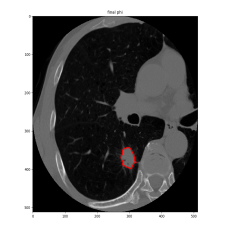

(1) Brain MR (2) Liver MR (3) Liver CT (4) Lung CT

We first introduce a method for connecting the output of a CNN to an ACM, yielding a model for the precise delineation of lesions, to which we refer as Deep Active Lesion Segmentation (DALS) (Figure 4). We then go further to introduce a truly unified framework (Figure 5) that bridges the gap between ACMs and CNNs by leveraging a novel, automatically differentiable level-set ACM with trainable parameters that allows for back-propagation of gradients and can be end-to-end trained along with a backbone CNN from scratch, without any CNN pre-training. The ACM is initialized directly by the CNN and utilizes an energy functional that is locally-tunable by the backbone CNN, through 2D feature maps. Thus, our work overcomes the big hurdle of fully automating the powerful ACM approach to image segmentation. We have applied our proposed framework to the task of building segmentation in aerial images (Figure 6).

Deep Active Lesion Segmentation

[45]: Lesion segmentation is an important problem in computer-assisted diagnosis that remains challenging due to the prevalence of low contrast, irregular boundaries that are unamenable to shape priors. We introduce Deep Active Lesion Segmentation (DALS), a fully automated segmentation framework that leverages the powerful nonlinear feature extraction abilities of FCNs and the precise boundary delineation abilities of ACMs. Our DALS framework benefits from an improved level-set ACM formulation with a per-pixel-parameterized energy functional and a novel multiscale encoder-decoder CNN that learns an initialization probability map along with parameter maps for the ACM. We evaluate our lesion segmentation model on a new Multiorgan Lesion Segmentation (MLS) dataset that contains images of various organs, including brain, liver, and lung, across different imaging modalities—MR and CT. Our results demonstrate favorable performance compared to competing methods, especially for small training datasets. -